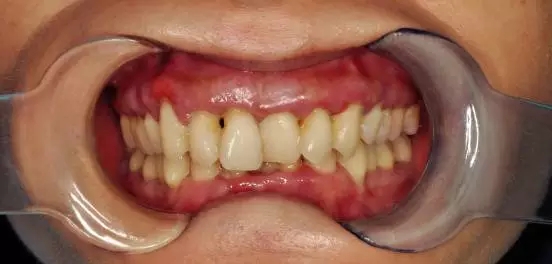

陸小姐,35歲,患者數(shù)月前發(fā)現(xiàn)下前牙松動(dòng),進(jìn)食時(shí)疼痛,刷牙出血;

檢查:全口口腔衛(wèi)生差,牙結(jié)石嚴(yán)重,牙齦紅腫,探之出血牙齒三度松動(dòng),前牙牙根暴露,X片顯示牙槽骨吸收嚴(yán)重

診斷:牙周炎(重度)

建議:全口清潔、齦下刮治,牙周治療

處理:洗牙、拋光、上藥